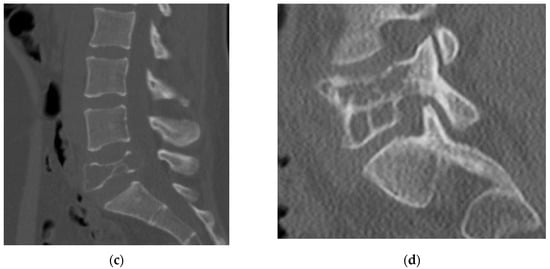

4.2.5. MRI